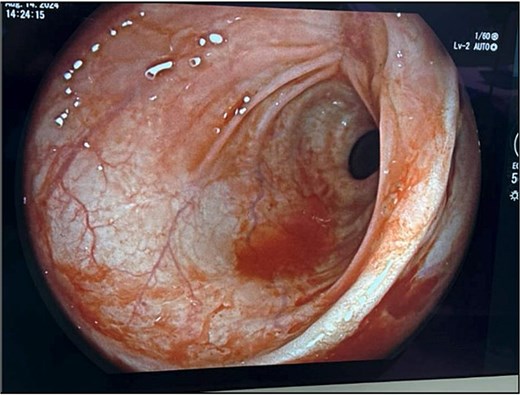

The patient’s leukocytosis resolved during hospitalization, and she was discharged on hospital day 5 with dietary modifications, including a low-fiber diet. At 4-week follow up, flexible sigmoidoscopy demonstrated near-complete healing of the rectal perforation, with only minimal residual mucosal disruption (Fig. 3). By 6 weeks post-injury, follow-up flexible sigmoidoscopy confirmed complete mucosal healing and restoration of normal rectal wall architecture, though mild rectal stenosis persisted (Fig. 4). The patient remained asymptomatic with resolution of her initial symptoms.

Flexible sigmoidoscopy at 6 weeks demonstrating complete mucosal healing and re-epithelialization at the prior perforation site, with no residual defect or inflammation.